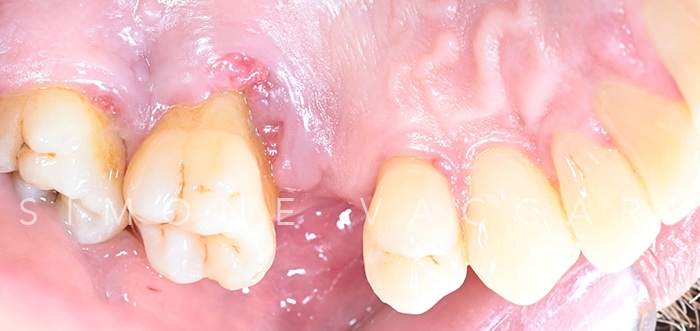

Michele bocca prima della cura della parodontite Prima

Michele arcata prima della cura della parodontite Prima